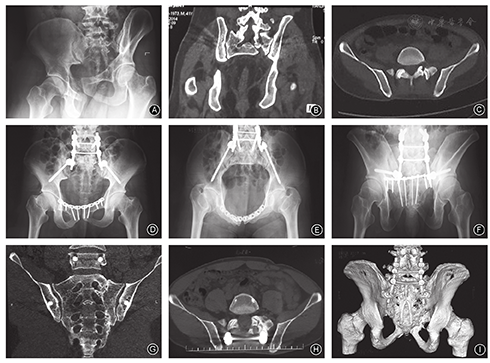

所有患者均于术后12~18个月行CT检查,结果示腰骶结合部达到骨性融合22例(图2),未融合16例(15例关节突关节对应关系良好,仅1例仍存在半脱位);骶骨骨折达到骨性愈合34例,2例未愈合(骨折线仍存在,边缘硬化,断端间瘢痕组织形成),2例部分愈合(断端仍存在骨缺损)。所有患者均在术后2.5年内取出椎弓根钉棒内置物。